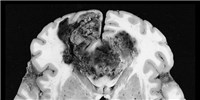

Acute myeloid leukaemia cells were particularly rife with bacterial sequences. A third of the microbial genes came from a genus called Acinetobacter, and had been inserted into the mitochondrial genome.